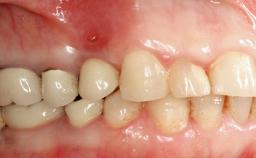

A 77-year-old male patient was referred for the management of frequent and repeated acrylic fracture of his existing mandibular fixed full-arch implant-supported metal/acrylic prosthesis. He also complained about softtissue soreness and the lack of retention and stability of his maxillary removable partial metal/acrylic prosthesis. Both prostheses had been delivered two years previously as part of his full-mouth rehabilitation (caries, tooth wear, tooth fracture). His medical history revealed high blood pressure, controlled with the use of antihypertensive medication.

SAC Level Complex

Defining Characteristics Fully edentulous lower jaw to be rehabilitated with an implant-borne fixed dental prosthesis

Inter-Arch Distance Excessive (mechanical leverage issues) or restricted (space for components)

Bruxism Present